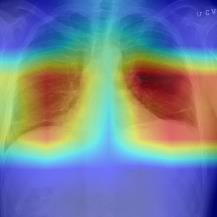

Thoracic disease detection from chest radiographs using deep learning methods has been an active area of research in the last decade. Most previous methods attempt to focus on the diseased organs of the image by identifying spatial regions responsible for significant contributions to the model's prediction. In contrast, expert radiologists first locate the prominent anatomical structures before determining if those regions are anomalous. Therefore, integrating anatomical knowledge within deep learning models could bring substantial improvement in automatic disease classification. This work proposes an anatomy-aware attention-based architecture named Anatomy X-Net, that prioritizes the spatial features guided by the pre-identified anatomy regions. We leverage a semi-supervised learning method using the JSRT dataset containing organ-level annotation to obtain the anatomical segmentation masks (for lungs and heart) for the NIH and CheXpert datasets. The proposed Anatomy X-Net uses the pre-trained DenseNet-121 as the backbone network with two corresponding structured modules, the Anatomy Aware Attention (AAA) and Probabilistic Weighted Average Pooling (PWAP), in a cohesive framework for anatomical attention learning. Our proposed method sets new state-of-the-art performance on the official NIH test set with an AUC score of 0.8439, proving the efficacy of utilizing the anatomy segmentation knowledge to improve the thoracic disease classification. Furthermore, the Anatomy X-Net yields an averaged AUC of 0.9020 on the Stanford CheXpert dataset, improving on existing methods that demonstrate the generalizability of the proposed framework.